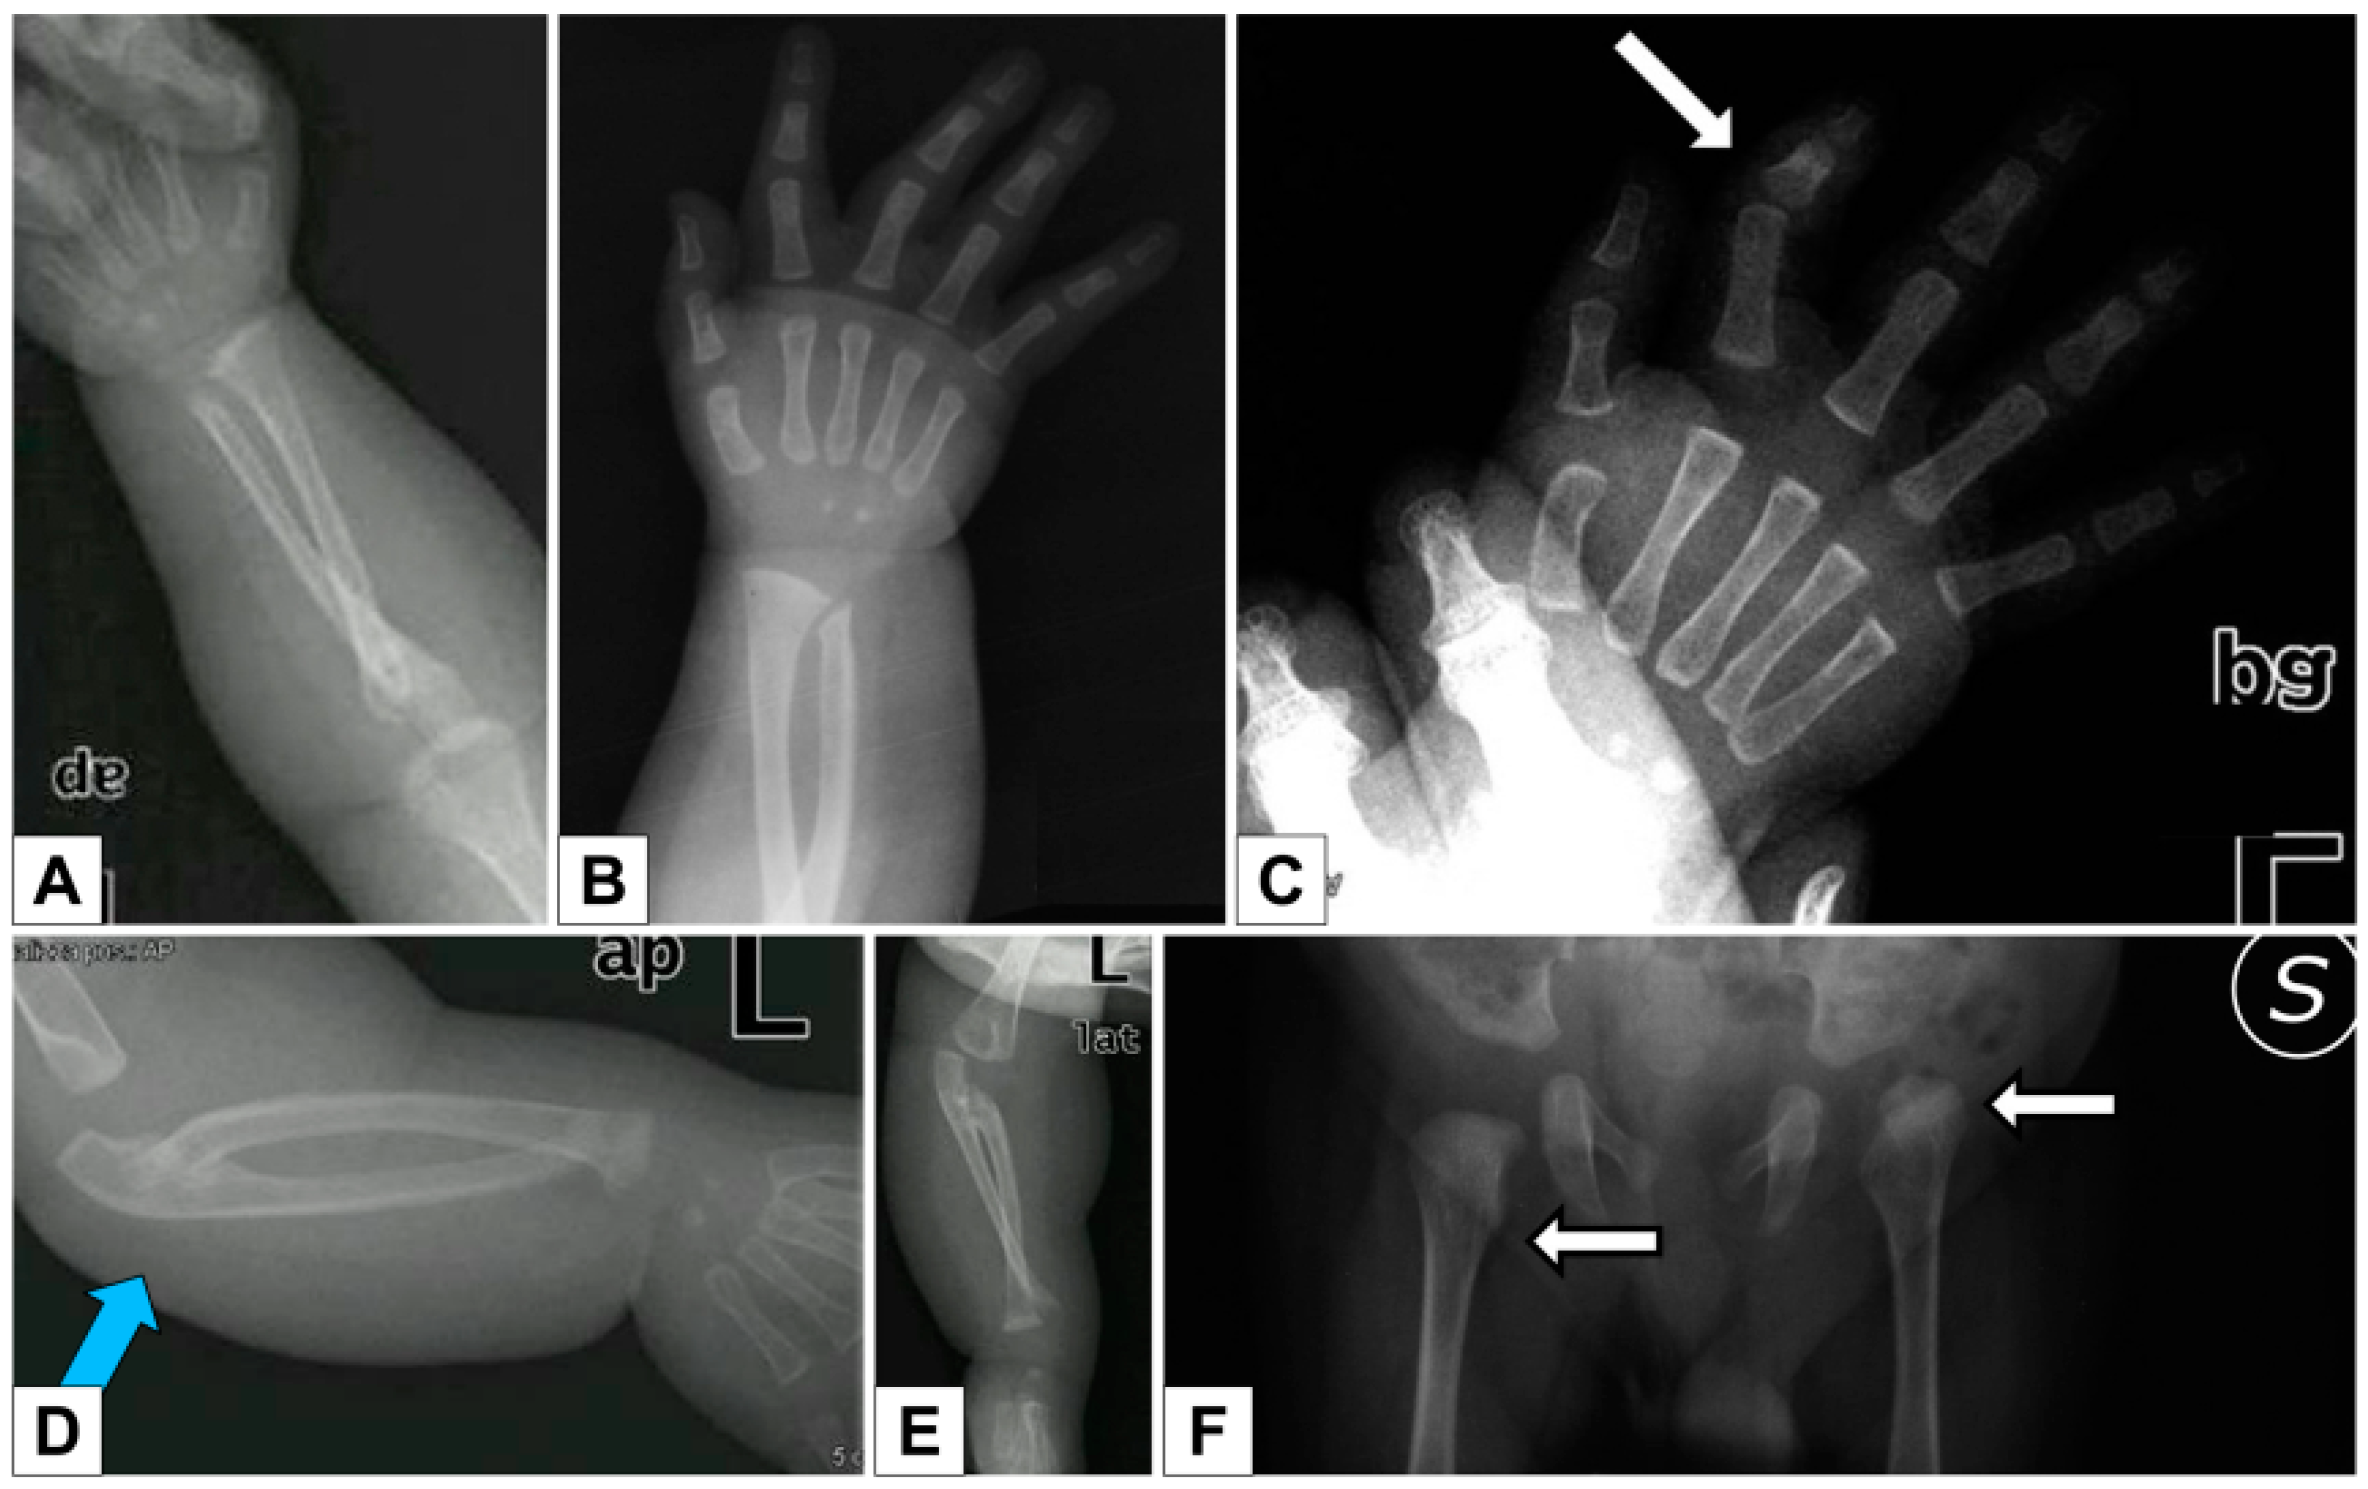

3.1.1. Clinical Report

- the extreme distal joint hypermobility and soft, hyperextensible skin, particularly of the hands;

- the radiological signs, which are the main indicator for discriminating spEDS-B4GALT7, associated with radioulnar synostosis, and spEDS-B3GALT6, characterized by kyphoscoliosis (congenital or early onset and progressive) and by the skeletal signs of SEMDJL1 (platyspondyly, short iliac bones, elbow dislocation).